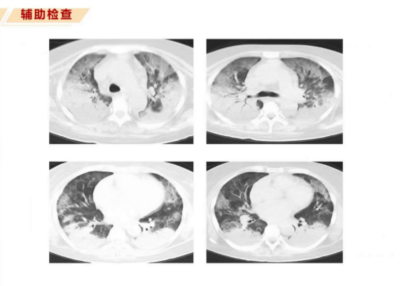

根据ARDS柏林定义,需符合四个诊断标准:明确诱因下一周内出现急性或进展性呼吸困难;影像学提示双肺弥漫性浸润性改变,不能完全由胸腔积液或肺不张解释;存在呼吸衰竭,不能用心力衰竭或容量过负荷解释;低氧血症。该患者符合重度ARDS标准。

但患者仍有间断发热、代酸、高钾血症及间断CRRT治疗。复查胸片提示双肺多发感染较前吸收,感染指标大致正常。支气管镜检查肺泡灌洗液培养为鲍曼不动杆菌,未调整抗感染治疗。6月27日复查胸部CT示双肺感染较前吸收好转,免疫科再次评估建议继续目前治疗方案,继续监测免疫相关指标。6月28日,患者氧合指数200 mmHg,行SBT试验30分钟后,氧合指数仍维持>200 mmHg,评估后予以脱机拔管,改经鼻高流量氧疗。

患者氧合指数逐渐升高,第18-22天二次评估后成功脱机拔管,从经鼻高流量氧疗过渡到面罩吸氧,氧合指数大于300 mmHg。7月8日复查CT显示双肺多发感染较前明显吸收好转,复方磺胺甲噁唑片抗感染治疗停药,患者可自主进食并进行床旁耐力训练。再次请免疫科会诊评估出院方案,调整为醋酸泼尼松片40 mg QD及硫酸羟氯喹片200 mg QD,出院半月后复查CT,8月1日CT较入院时明显吸收好转。